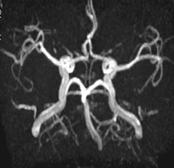

Explorari vasculare: arteriale, venoase

TOF 2D sau 3D

PC 2D, 3D

T1 SE cu GD: incarcarea structurilor anatomice normale:meninge (coasa creierului si cortul cerebelos), plexuri coroide, antehipofiza, epifiza, tija pituitara, vene, mucoasa sinusurilor, retina. Arterele din cadrul poligonului Willis nu se incarca postGD in T1 SE datorita fenomenului de iesire din sectiune a H+.

Imagini sursa 3DTOF MIP